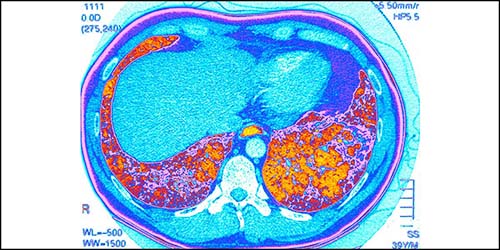

Clinicians from Columbia and Weill Cornell Medicine are at the forefront of pulmonary medicine and lung surgery combine leading-edge therapies with compassionate care for patients with all types and stages of lung disease. Our researchers are contributing to promising advances in acute lung injury, COPD, interstitial lung disease, and pulmonary hypertension.

Pulmonology & Lung Surgery